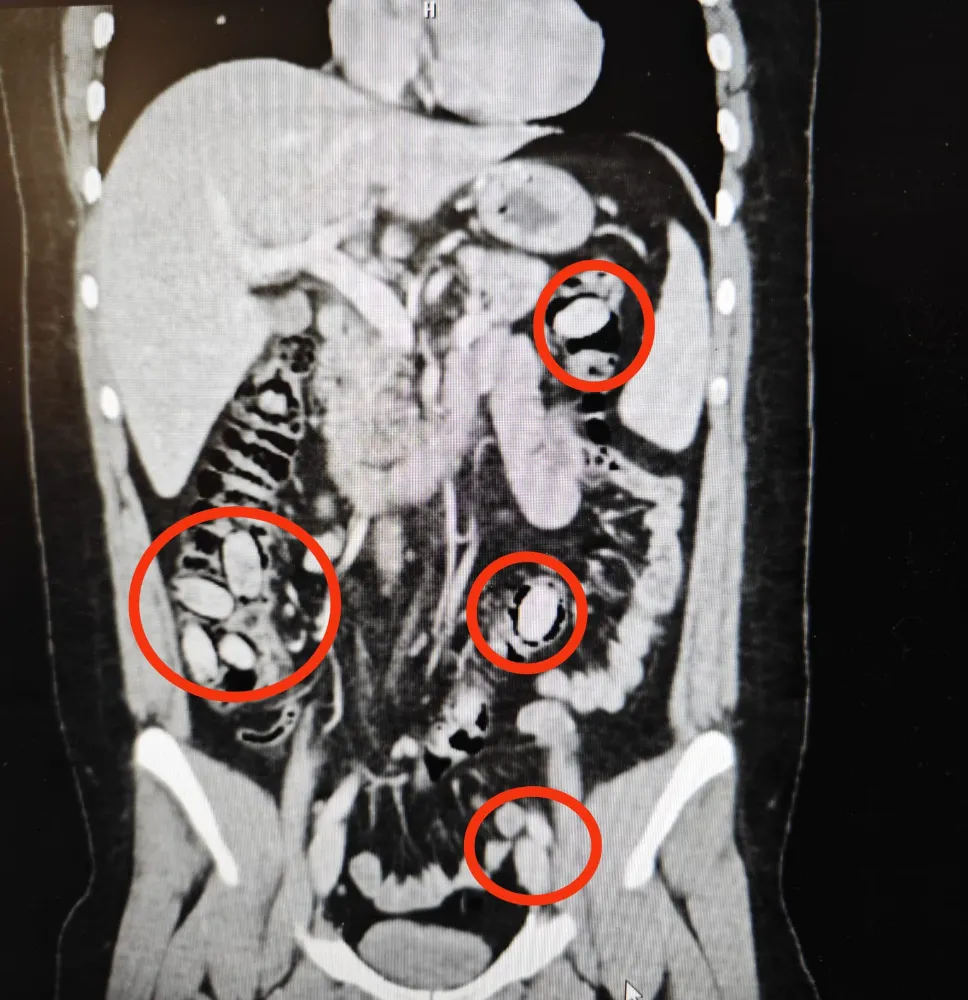

Eskişehir Emniyet Müdürlüğü ekipleri, yurtdışından Eskişehir’e geldiği belirlenen S.A.’yı kent girişinde durdurdu. Sürekli midesini tutmasından şüphe edilmesi üzerine S.A., hastanede sağlık kontrolünden geçirildi. Şüpheli S.A.’nın hastanede çekilen röntgeninde midesinde 44 kapsül olduğu tespit edildi. Eskişehir Cumhuriyet Başsavcılığı’nın talimatıyla cerrahi müdahaleye alınan S.A.’nın midesindeki 44 kapsül çıkarıldı. Kapsüllerde yapılan incelemede içerisinde uyuşturucu metamfetamin (bonzai) maddesi olduğu belirlendi.